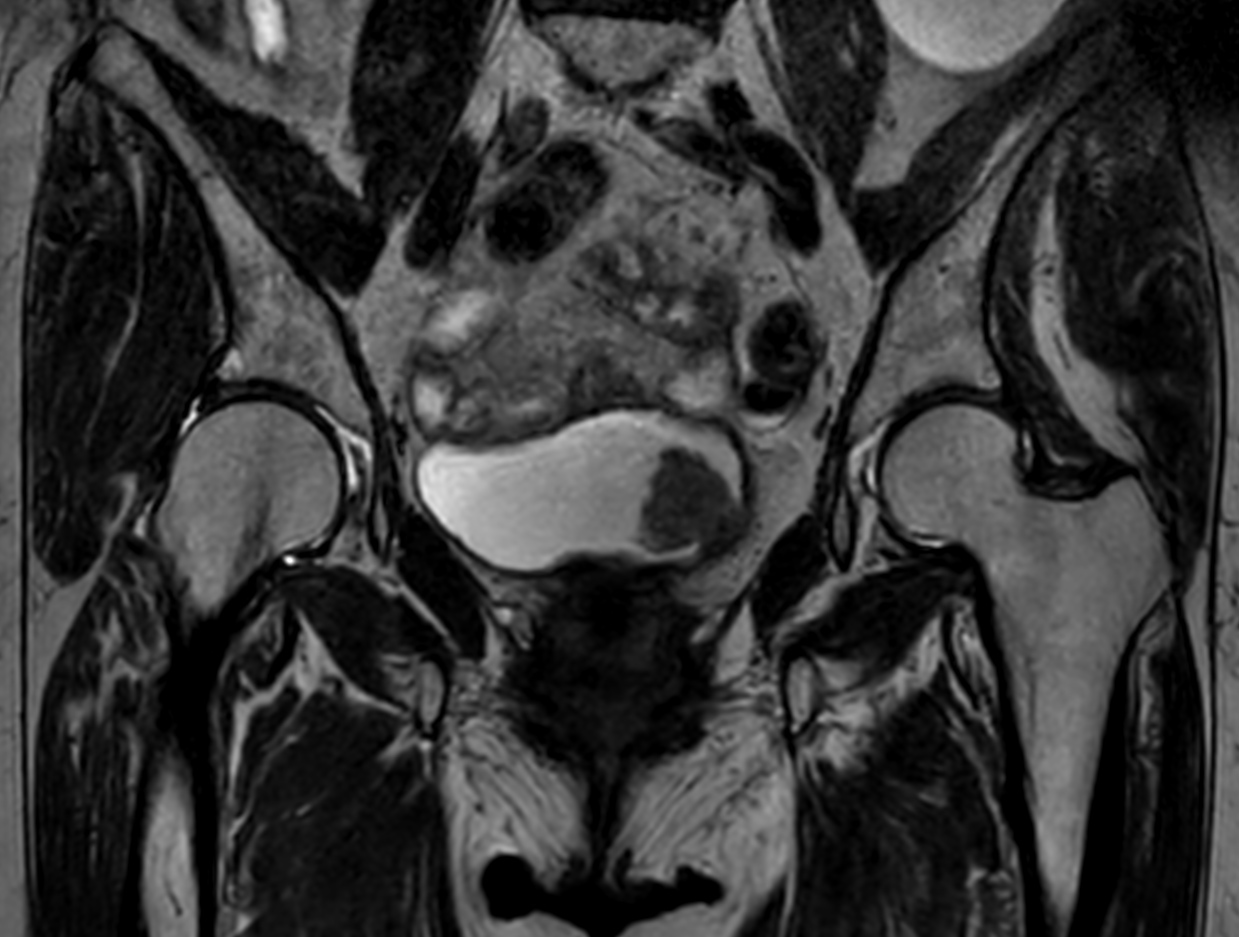

3D T2w TSE PelvisVIEW Compressed SENSE

3D T2w TSE PelvisVIEW (reformat) Compressed SENSE